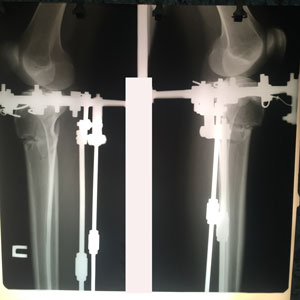

на фиксации

IMG_5699-10-09-19-09-32.JPG

IMG_5673-09-09-19-09-39.JPG

IMG_5672-09-09-19-09-39.JPG